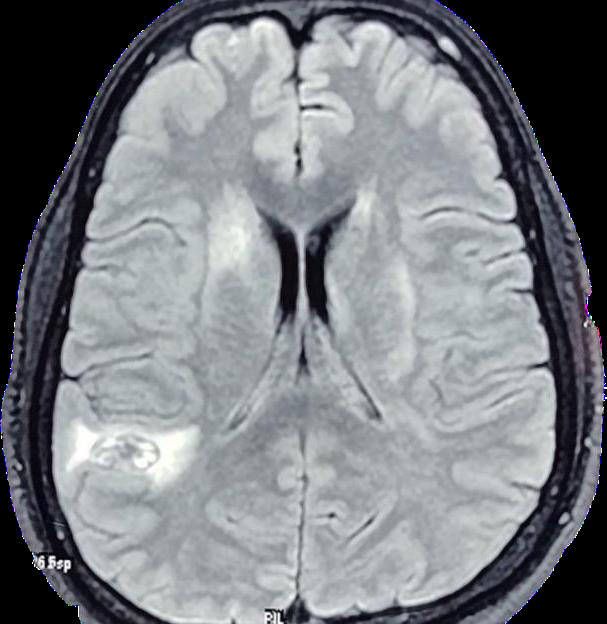

Figure 1:Well defined area of T2/FLAIR of heterogeneous hyper-intensity

with surrounding peri-lesional edema noted in right temporo parietal lobe.

Intra cerebral hematoma in right parieto occipital lobe with

peri-lesional edema

Multiple micro-bleeds and punctate microhemorrhages

dispersed in bilateral brain parenchyma

Confluent T2/FLAIR hyperintensities in bilateral deep

cerebral white matter.

Post-contrast imaging: Perivascular enhancement along

vessels in bilateral cerebral hemispheres

The turning point in diagnosis was the detailed review of

sequential MRI findings, which revealed microhemorrhages in the

cerebellum and brainstem, along with perivascular enhancement and

MR angiography revealing skipped and segmental pattern of vessel

involvement — features more characteristic of PACNS than TB. The